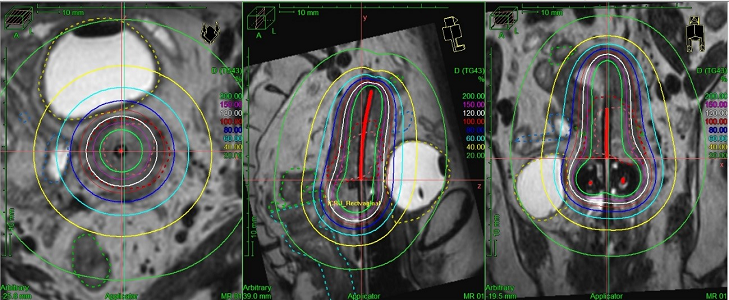

RALS

小線源治療には、ラルス(RALS:Remote After Loading System)という専用の医療機器が多く用いられます。この機器を用いて、粒状の小さな放射線源を身体の中に入れ、身体の中から放射線を当てる方法です。そのため、放射線を病変に限局し、かつ集中的に照射できるようになっています。従来は単純X線画像を用いて治療計画を行っていましたが2014年よりCT画像やMR画像を用いた三次元画像誘導密封小線源治療を開始しました。単純X線画像ではわからなかった腫瘍やリスク臓器が可視化できるため、より腫瘍に限局した照射ができリスク臓器の線量を下げることが可能になりました。